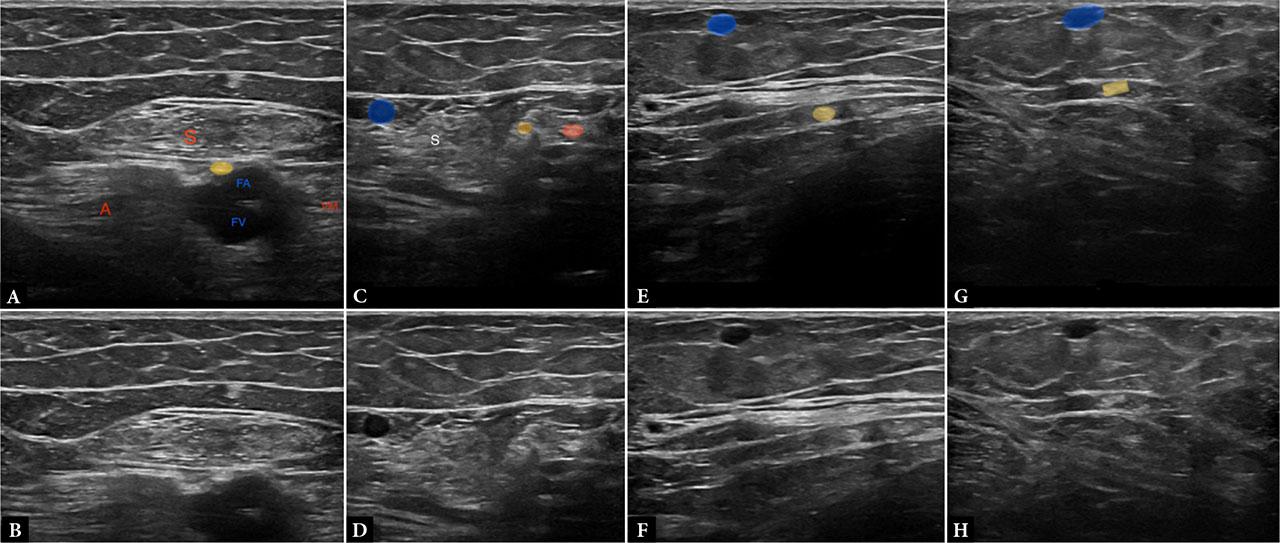

The saphenous nerve courses along the medial aspect of the thigh, positioned lateral to the femoral vessels, and passes through the adductor canal beneath the sartorius muscle. In the lower half of the canal, it lies deep to the vastoadductor membrane, while the nerve to the vastus medialis remains superficial. Distally, thickening of the vastoadductor membrane represents a potential site for nerve entrapment. The saphenous nerve gives rise to the infrapatellar branch in the lower thigh, immediately distal to the adductor hiatus. Following the origin of the infrapatellar branch, the main trunk accompanies the saphenous branch of the descending genicular artery along the medial aspect of the leg. At a variable level, it pierces the crural fascia to enter the subcutaneous plane, where it lies in close association with the great saphenous vein(2,20) (Fig. 11).

Images A and B demonstrate the normal saphenous nerve (yellow) within the adductor canal, deep to the sartorius (S) and the vastoadductor membrane between the vastus medialis (VM) and adductor magnus (A). Images C and D show the saphenous nerve (yellow) after piercing the vastoadductor membrane and giving rise to the infrapatellar branch (green). Note its proximity to the great saphenous vein (blue). Images E and F demonstrate the saphenous nerve (yellow) in the lower medial thigh before piercing the medial muscular septum. In images G and H, the nerve (yellow) lies in the subcutaneous plane in close relation to the great saphenous vein (blue)